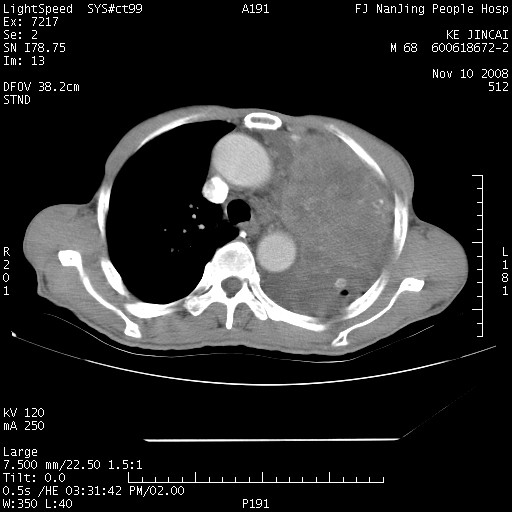

是个很有看头的病例,咋人气那么不旺?没多少人兴趣呢?这个病例几大怪:1   恶性肿瘤侵犯心肌左房怪,心肌一般不会被恶性肿瘤侵犯吧?2   左下肺均匀实变怪,内无含气,有别一般不张实变,含气肺泡完全为液体取代,而非一般不张实变的肺萎陷,冷不丁还以为是肿大的脾脏3   肿瘤本身怪,像tb肺不张4   这么有看头的病例没人气怪。呵呵。

左肺恶性肿瘤侵犯肺动脉,左心房内瘤栓,胸膜转移。